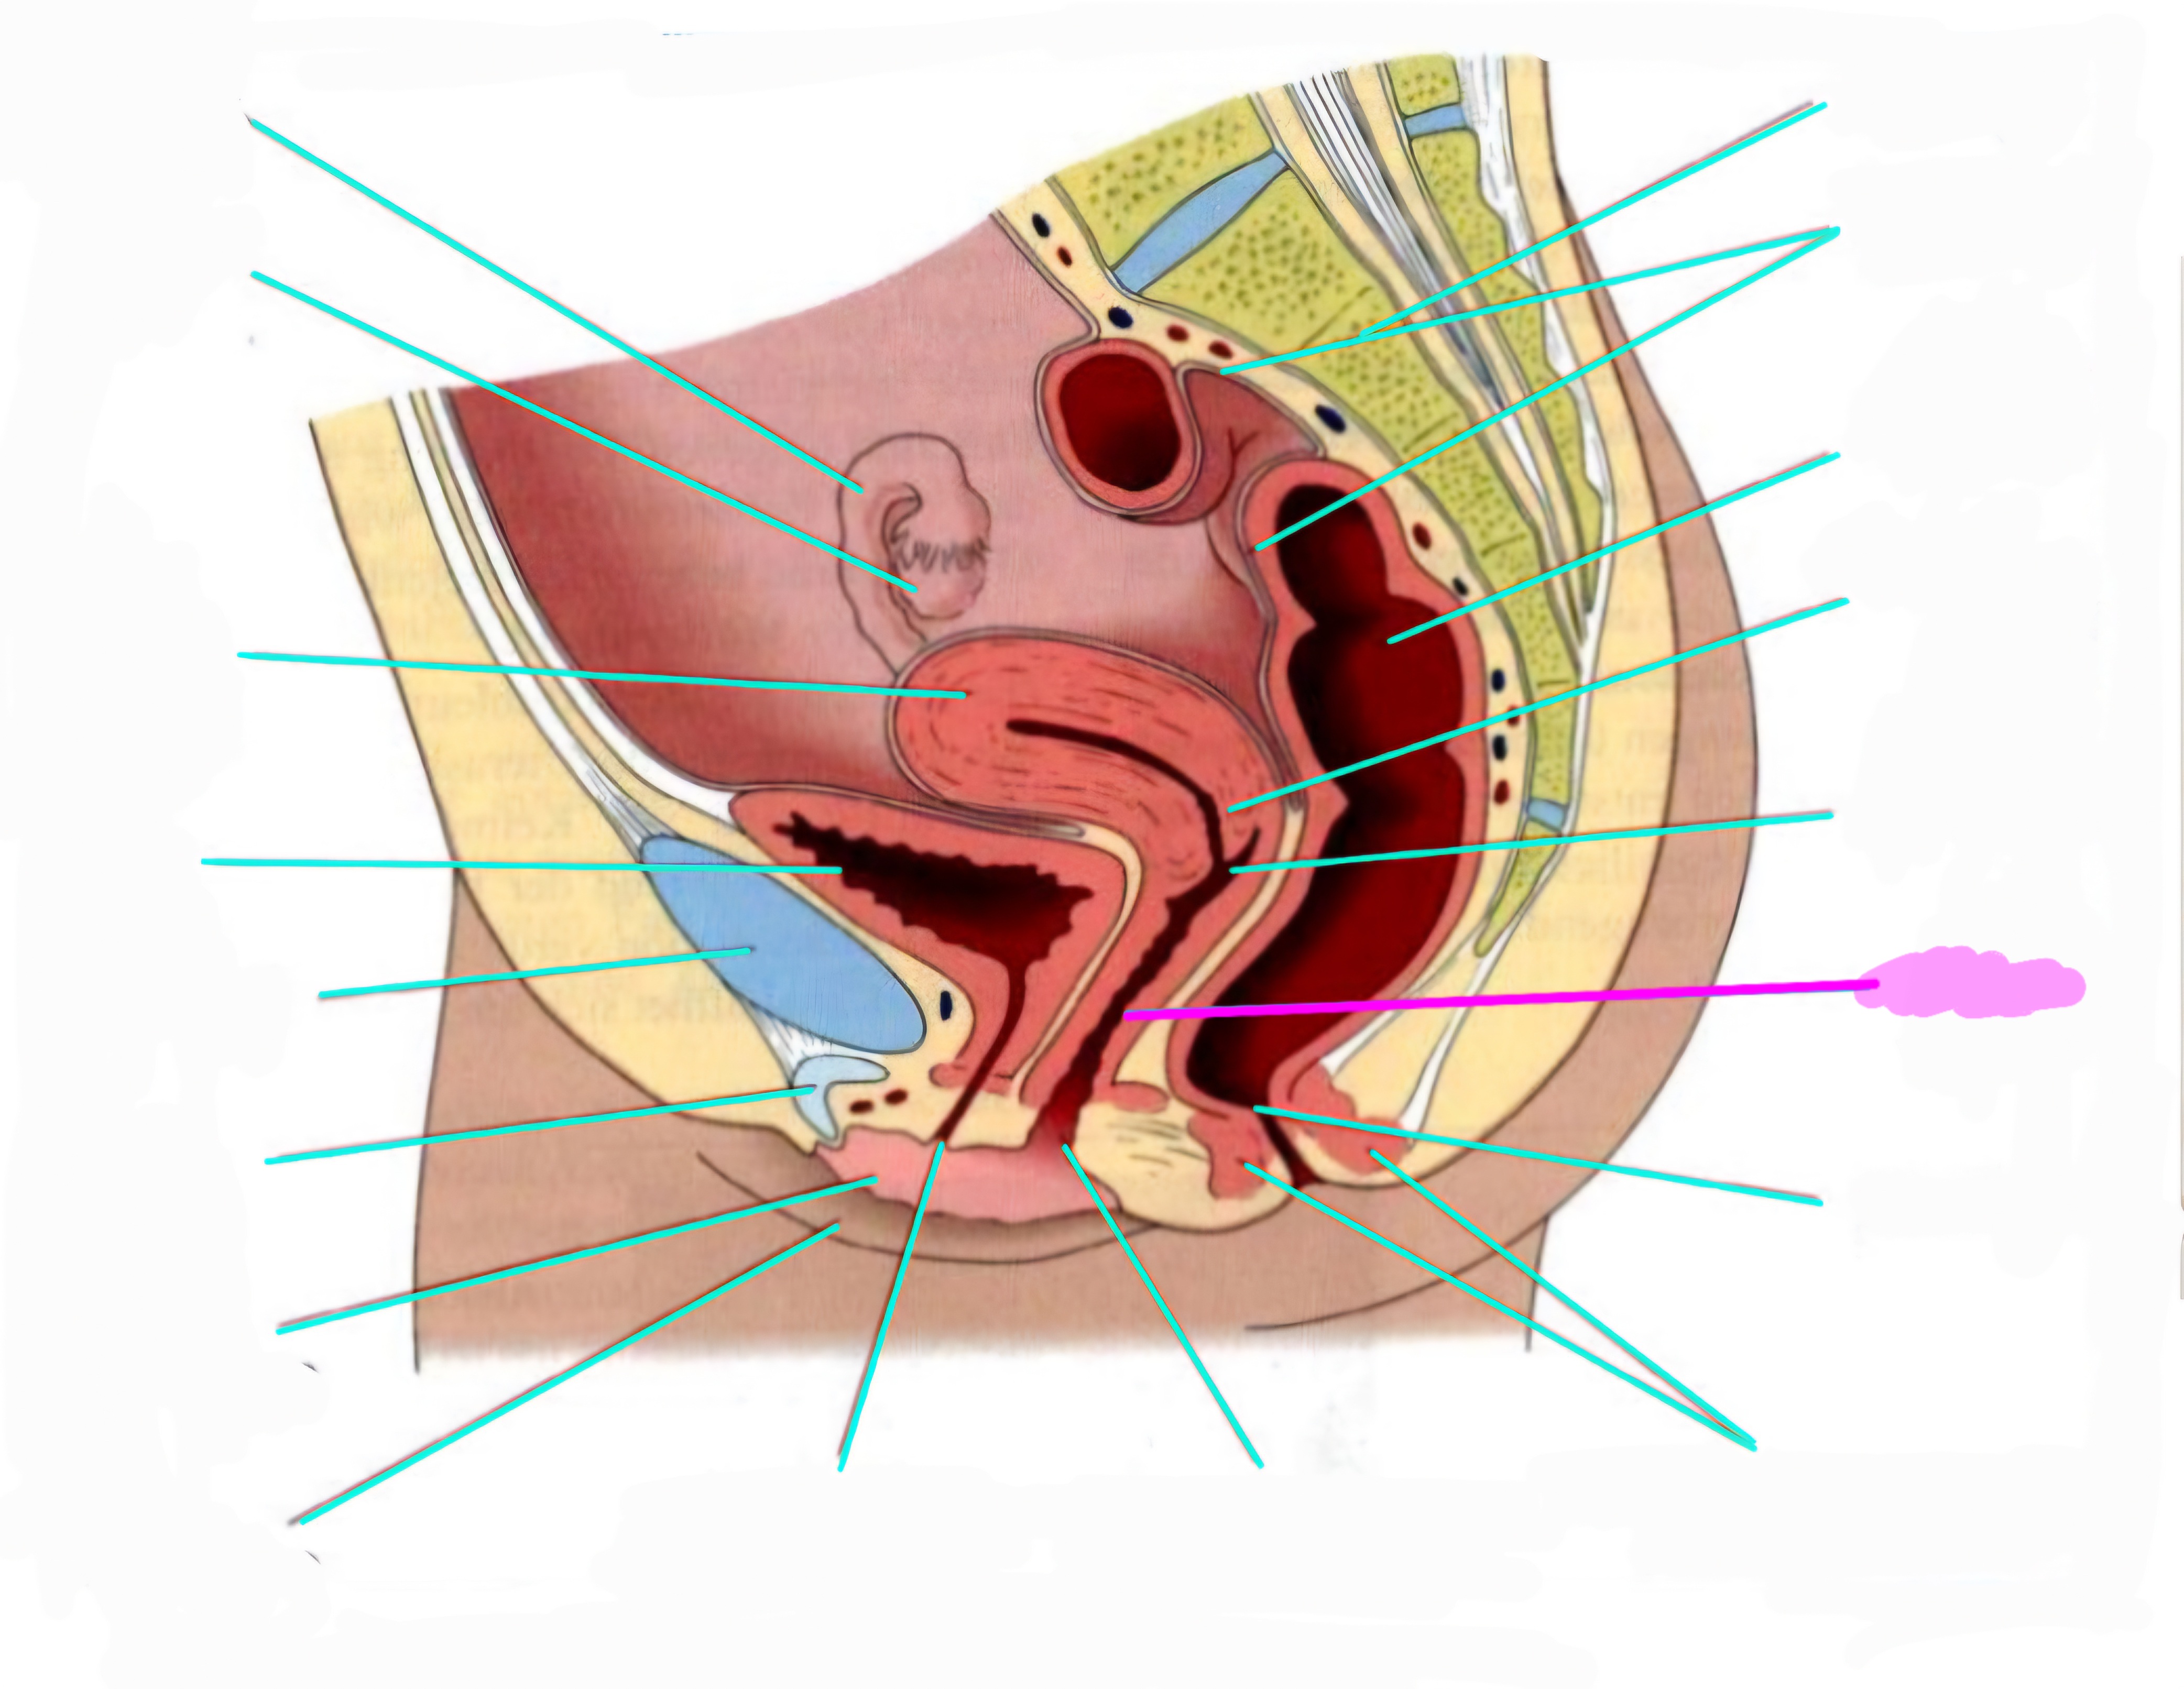

wbl. genital Anatomie

19 Terms

Tubea uterina (Eileiter)

Ovar (Eierstock)

Uterus (Gebärmutter)

Vesica Urinaria (Harnblase)

Symphyse

Klitoris

Labia minor pudendi (kleine schamlippen)

Labia Majoran pudendi (große Schamlippe)

Urethra (Harnröhre)

Introitus vaginae (Scheideneingang)

Sphincter ani externes (äußere Afterschließmuskel)

Anus (After)

Vagina (Scheide)

Portio (äußerer Muttermund)

Rektum (Mastdarm)

Zervix (Gebärmutterhals)

Peritoneum (Bauchfell)

Os sacrum (Kreuzbein)

Uterus: Topographie und Aufbau - wie groß ist er und wo liegt er?

7-8cm lang, Form einer umgedrehten Birne

Lage: im kleinen Becken zwischen Blase und Rektum

Antiversio: nach vorne geneigt, steht im Winkel zur Scheide

Antiflexio: in sich selbst geknickt, nach vorne abgebogen öber die Blase